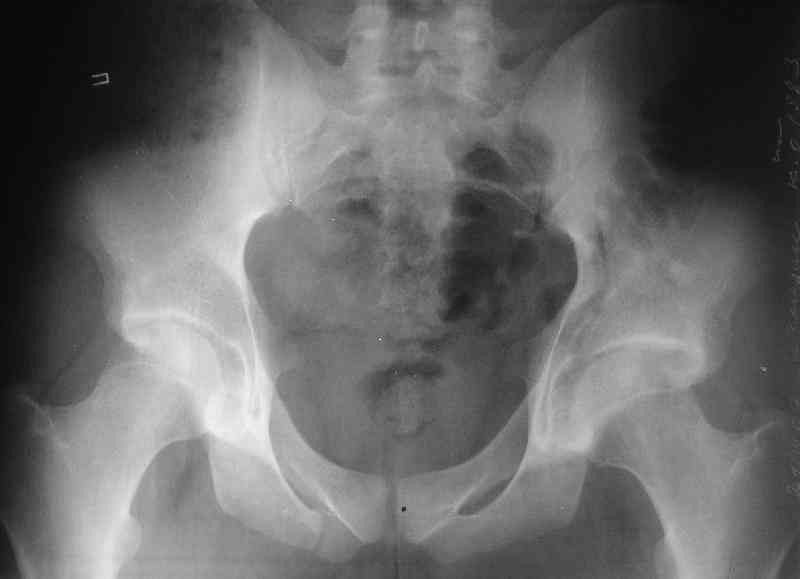

What is your indication for surgical management? What kind of fracture do you think it is? It looks like a transverse type although it has been a couple of years since I looked at an acetabular fracture.

Displaced acetabular fractures are a challenging problem. In contradistinction to most conditions in which surgery is based on specific operative indications, displaced acetabular fractures should be considered an operative problem unless specific criteria for nonoperative management are met. These include a congruent hip joint on the anteroposterior and oblique (Judet) radiographs, an intact weight-bearing surface (as defined by roof arc and subchondral arc measurements on computed tomographic scans), and a stable joint. The final decision about the treatment method must also consider the patients functional demands, expectations, and physical condition and the physicians experience and institutional support for dealing with this type of injury. Displaced both-column fractures with secondary congruence may have better results than other displaced fractures.

My concern would be that the risk of leaving it malreduced is very high. It appears to be primarily a gap rather than a step in the articular surface. Do you have any CT views that show an articular step?

The last two images from the 3-D CT scan certainly makes the fracture look worse than the plan radiographs.

The anterior element of the fracture is so low and the anterior roof arc angle must be at least 60 deg.

The posterior element is so minmally undisplaced. There is good congruence of the joint, and to top it all, 6 weeks have passed. If you consider ORIF now, I don't expect that much improvement could be accomplished. Not to mention the need for extensive approaches with their morbidity.